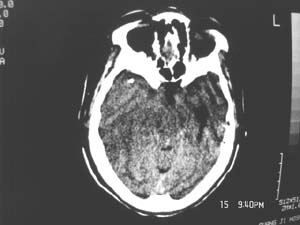

女,60岁,反复头痛3天,呕吐3小时伴昏迷10分钟入院检查。

右额叶占位,有占位效应,中线偏移,病灶位于镰旁,呈囊实性并有钙化,

考虑:1.脑膜瘤。2.胶质瘤。

理由:1.病灶位于前颅凹及镰旁,有明显占位效应---支持脑膜瘤。

2.病灶呈囊实质性并有条状钙化,符合胶质瘤改变;

另外也不排除包虫病的可能。

2、提示蛛网膜下腔出血(少量)。

支持脑膜瘤(少枝胶质瘤)、蛛网膜下腔出血

病变范围较大,累及左额叶,内见钙化。及高密度灶。考虑;胶母伴卒中可能大。